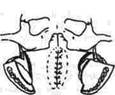

| Рис. 314. Схема подниж-нечелюстного и полувенечного доступов, линии остеотомии нижней челюсти и скуловой кости. |

Остановимся на первом хирургическом доступе, который нами назван как ТРАНСФАЦИ-АЛЬНЫЙ ДОСТУП К крылонёбной, ПОДВИСОЧНОЙ ОБЛАСТЯМ И СРЕДНЕЙ ЧЕРЕПНОЙ ЯМКЕ (В. А. Маланчук, Ю. А. Зозуля, В. и. Цымбалюк, О. А. Цымейко, Л. В. Бондарь). В этом доступе различаем четыре этапа.

1-й этап. Из окаймляющего угол нижней челюсти доступа (рис. 314) обнажаем нижний край угла челюсти. Накладываем провизорную лигатуру на наружную и внутреннюю сонную артерии (НСА и ВСА), перевязываем верхнечелюстную артерию (рис. 315). Затем проводим кпереди от жевательной мышцы фигурную поперечную остеотомию тела нижней челюсти, чем достигаем мобильности ветви челюсти. Через созданные в области угла челюсти отверстия проводим лигатуру, на которой поднимаем ветвь челюсти кнаружи и освобождаем доступ в нижние отделы подвисочного пространства и в крыло-челюстное пространство (после отслойки наружной крыловидной мышцы). При необходимости пересекаем на лигатурах двубрюшную мышцу и заранее готовим отверстия на фрагментах нижней челюсти для последующего ее остеосинтеза. Затем проводим выделение нижних отделов опухоли подвисочной области и крылонёбной ямки.